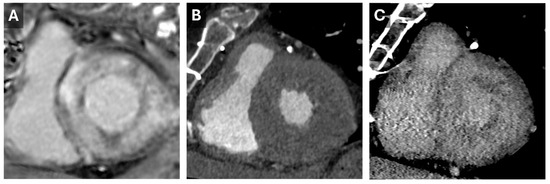

Current protocols involve both non-contrast and contrast-enhanced acquisitions, followed by a delayed phase approximately 5–10 min later []. The contrast volume used is often at least 1.5 mL/kg, which is higher than for coronary assessments. Iodinated contrast behaves similarly to gadolinium accumulating in abnormal myocardium with greater extracellular space, such as in areas of diffuse fibrosis or amyloid deposition (Figure 5), which allows for more accurate disease detection.

Figure 5. Cardiac Amyloid Findings. CMR short-axis delayed-enhanced inversion recovery image through the LV base (A) from a patient with severe cardiac amyloidosis with diffuse transmural delayed enhancement. Short axis images through the LV base from a previous cardiac CT with arterial (B) and 5 min delayed (C) phases. The delayed phase demonstrates diffuse nonvascular enhancement that correlates well with the findings seen on the subsequent CMR.

Despite its advantages, CT for ECV measurement has limitations, including a low signal-to-noise ratio and the need for higher contrast doses. Dual-energy CT can address some of these issues by reducing contrast requirements and utilizing varying tube potentials (Figure 6) []. This approach was validated in 2020 when Ohta et al. demonstrated a significant correlation between CT- and CMR-based ECV quantification in 23 patients [].

Figure 6. Dual-energy Cardiac CT Imaging. Short-axis reconstructions through the LV base from a 5 min delayed phase of a contrast-enhanced cardiac CT that utilized spectral (dual energy) technique. Images from the high-energy (A) and low-energy (B) datasets show the increase in iodine conspicuity from the low-energy data (B). A virtual monoenergetic 50 keV reconstruction (C) demonstrates a good mix of anatomic information and contrast conspicuity.